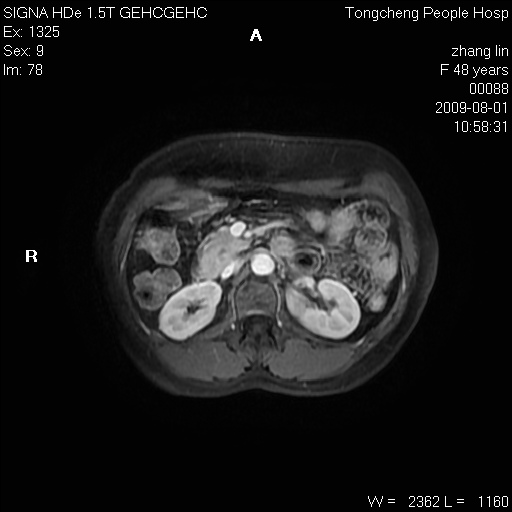

女,48岁。健康体检,彩超发现右肾占位性病变。平素健康。

临床诊断:右肾占位性病变,性质待定(囊肿?肿瘤?)。

上中腹部mr平扫+增强扫描,图像如下:

右肾上极见一类圆形病灶,t1wi呈等信号t2wi呈等高混杂信号,三期增强无强化,边界清---考虑囊肿出血。

同反相位均表现为等信号,病变无强化,考虑含蛋白的囊肿可能,弥散加权相或许有些帮助,

肝囊肿

慢性胆囊炎